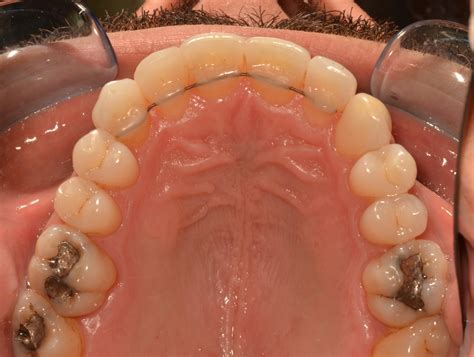

Orthodontic Correction of Midline Diastema in Aggressive Periodontitis

Orthodontic Correction of Midline Diastema in Aggressive Periodontitis ...